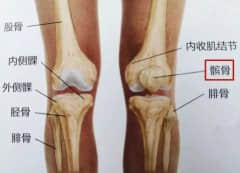

膝盖痛、腿变形?一定要警惕这个病

膝关节骨性关节炎的临床表现